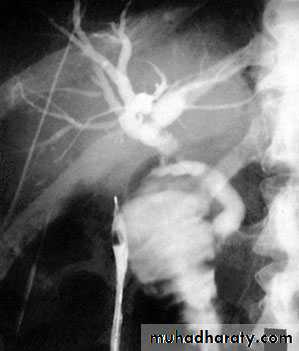

66Transhepatic cholangiogram showing a stricture of thecommon hepatic duct

almadena copy